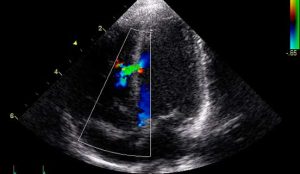

ECOCARDIOGRAFIA